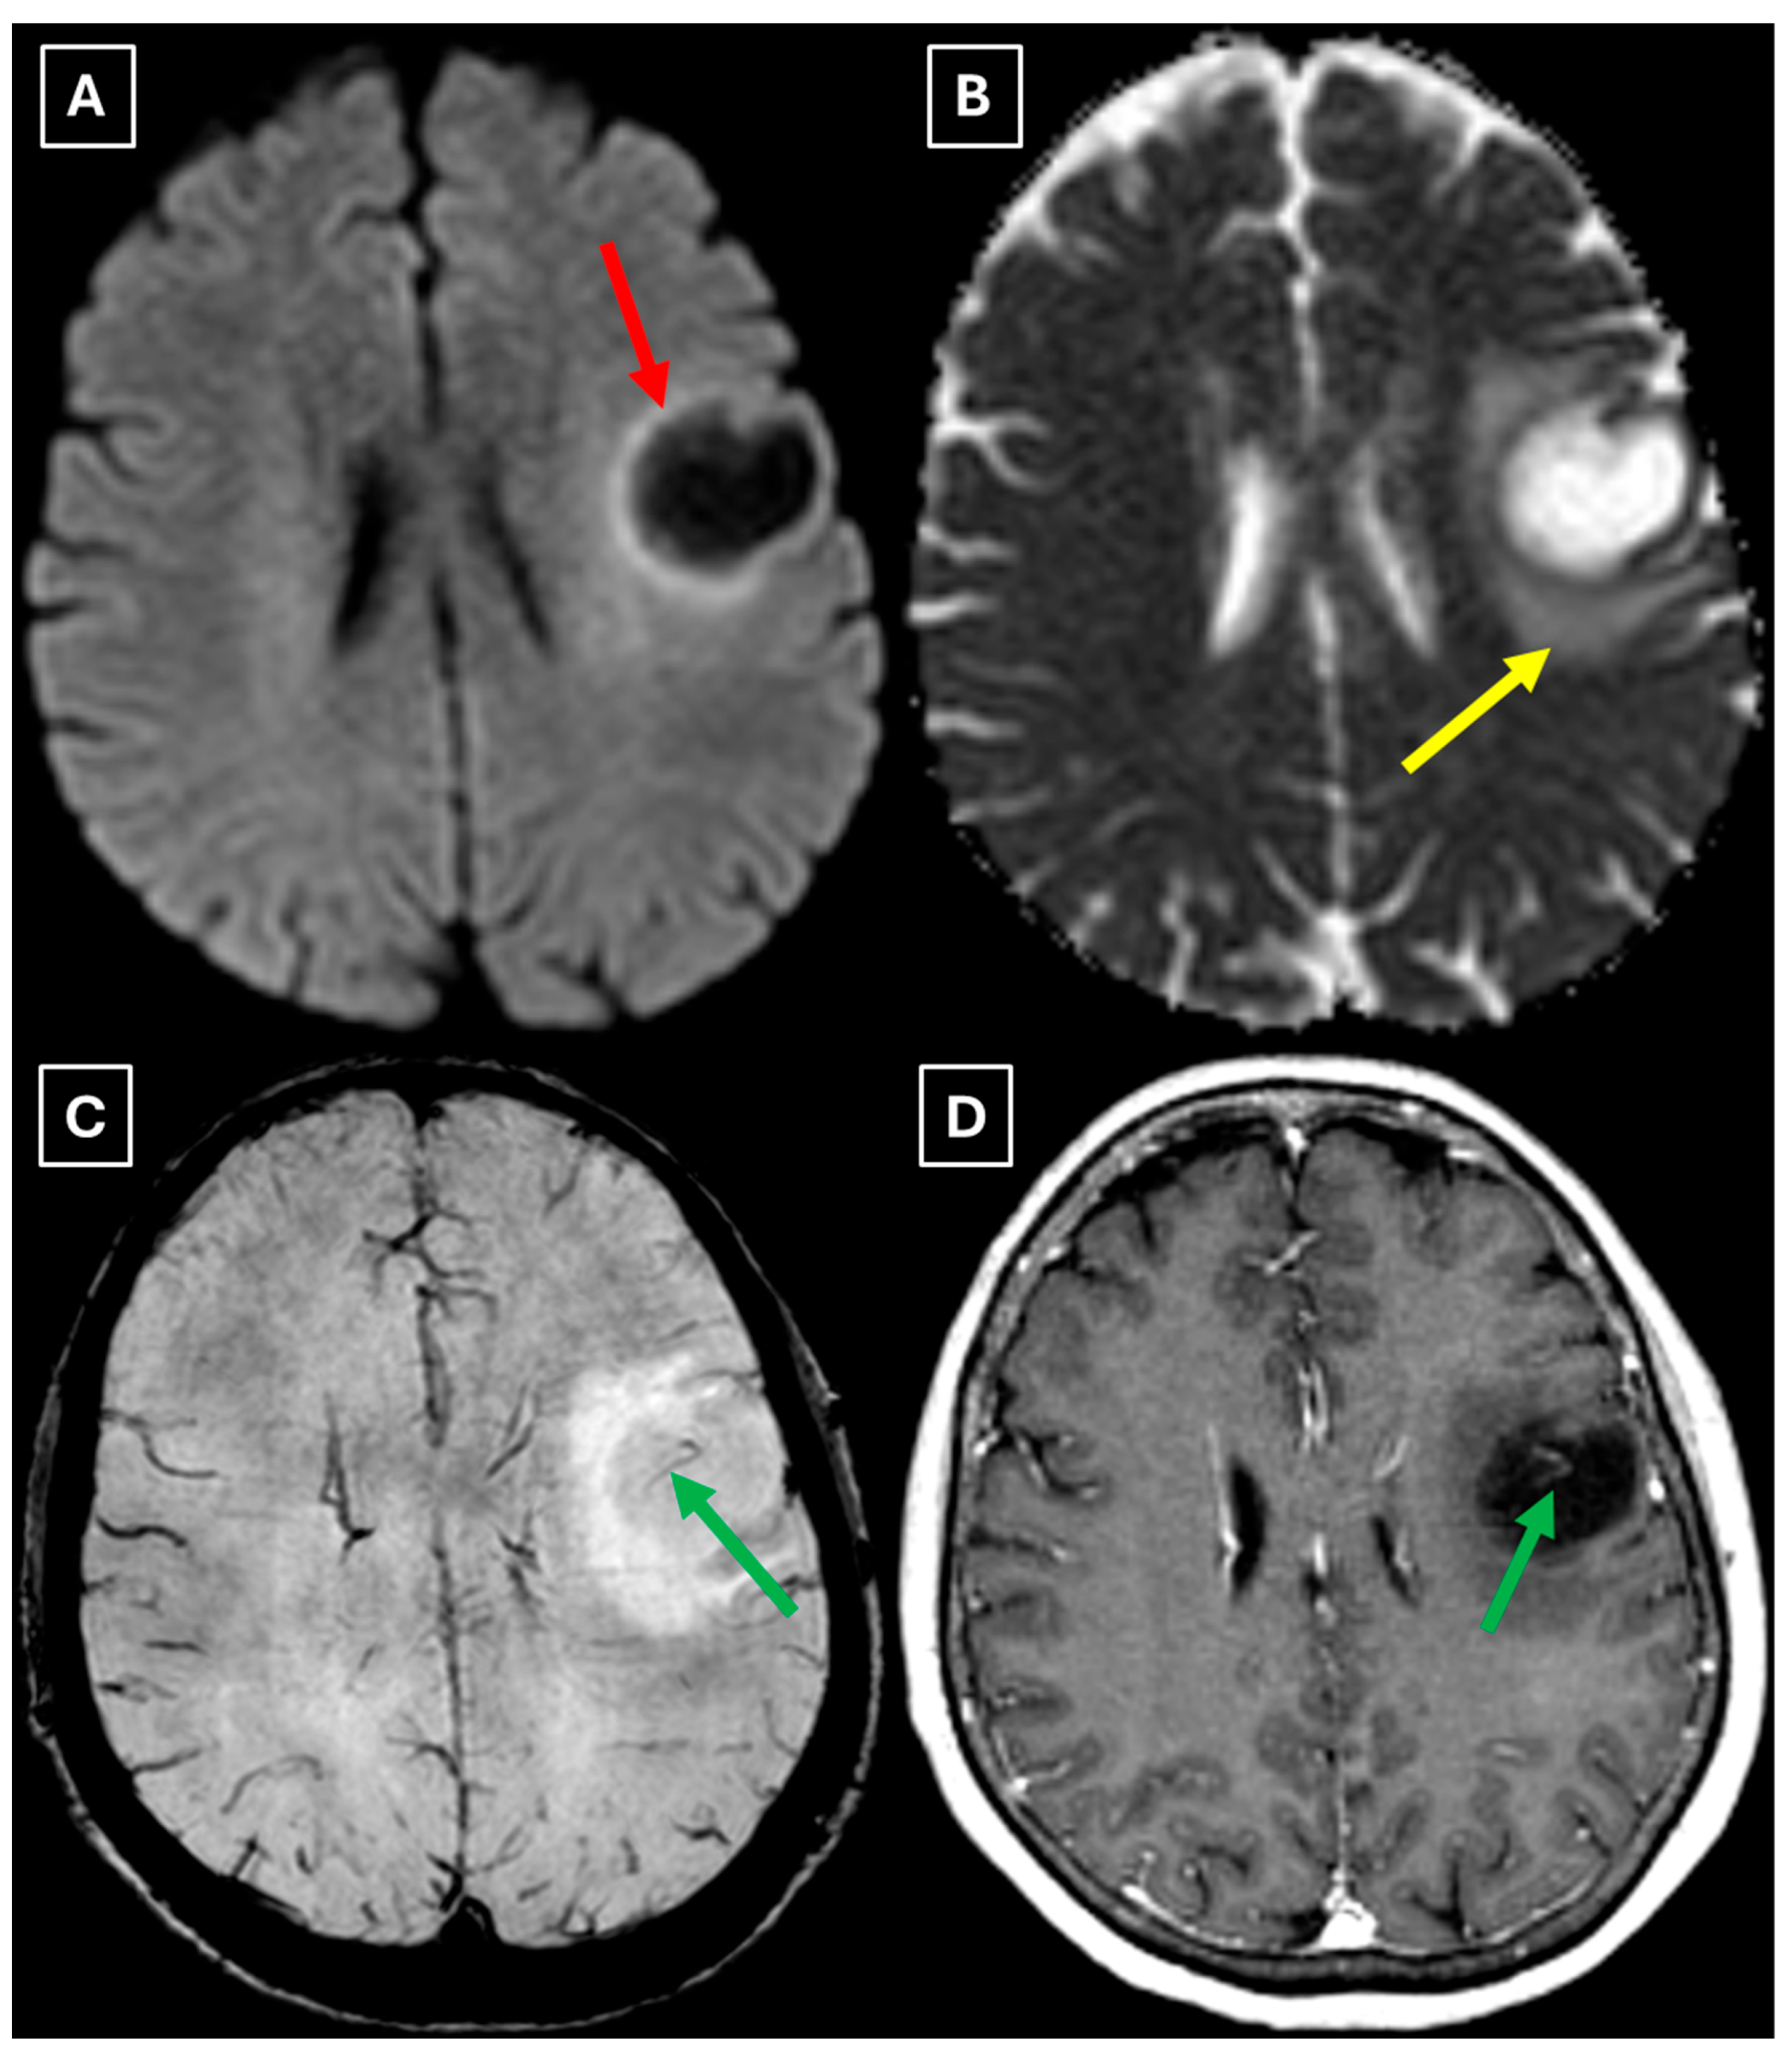

A repeat MRI before surgery showed that the lesion had reduced in size with no pathological contrast uptake persistence, with surrounding perifocal edema (Figure 4 and Figure 5). Given the improved results, the medical team suspected a demyelinating disease rather than a tumor and surgery was canceled. For diagnostic purposes, a lumbar puncture was performed. Cerebrospinal fluid (CSF) analysis excluded neuroinfection. Blood tests and CSF were examined according to the demyelinating disease protocol. Oligoclonal antibodies were negative in both the CSF and blood serum. Aquaporin-4 (AQP-4) antibodies were not found in the blood serum, and myelin oligodendrocyte glycoprotein (MOG) antibodies were also negative.

Figure 4. Two-week follow-up MRI scan of the brain. (A): Axial T2-weighted image shows a hyperintense and homogenous left frontal lobe lesion with well-defined borders. The lesion decreased from 37.34 mm × 34.85 mm (AP × LL) to 24.87 mm × 29.71 mm (AP × LL). A relatively extensive perifocal edema again persists, involving the white matter with relative spare of the white matter adjacent to gray matter; however, there is no mass effect or midline shift. (B): In the axial FLAIR the lesion appears with a more hypointense center and hyperintense peripheral rim at the lesion margins. Given the observed changes over a 2-week period and the decrease in the lesion’s size, an astrocytoma is considered less likely. Red arrow—indistinct formation, yellow arrow—perifocal vasogenic edema.

Figure 5. Two-week follow-up MRI axial scan of the brain. (A): Axial trace from diffusion-weighted imaging shows a higher signal along the peripheral parts of the lesion with the absence of cytotoxic edema when correlated with (B): the ADC map. (C): Central vein sign is positive on the susceptibility-weighted imaging sequence and (D): axial postcontrast T1-weighted sequence. These findings were not typical for low-grade astrocytomas. Red arrow—diffusion restriction, yellow arrow—perifocal vasogenic edema, green arrow—central vein sign.

Finally, we provide a high-resolution MRI follow-up of two months’ duration showing near-complete regression of the lesion after corticosteroid therapy. The lesion decreased from 37.34 mm × 34.85 mm (AP × LL) to 24.87 mm × 29.71 mm following two weeks of corticosteroid therapy and after almost two months from the first MRI scan to minimal patchy contrast enhancement (Figure 7D). This marked decrease in the size of the lesion gives strong evidence that a demyelinating rather than neoplastic process is present.

We also found similarities between this case and the classical imaging features of TDLs described in the literature. Hypoattenuation on noncontrast CT corresponding to enhancing areas on MRI is another useful imaging finding in TDLs [10], which may be explained by the tissue rarefaction caused by the active demyelination rather than increased cellularity, which is seen in tumors, thereby supporting the use of MRI with noncontrast CT in TDL diagnosis. Furthermore, restricted diffusion along the lesion margin with elevated central ADC values, in contrast to neoplasms which more commonly show central diffusion restriction, have been described as a commonly presenting feature of TDLs [3,4,10], which was also observed in this case (Figure 5A,B).

In this case, despite the presence of a T2/FLAIR mismatch sign (Figure 2), several imaging characteristics were more suggestive of a TDL rather than IDH-mutant astrocytoma. The lesion was located in juxtacortical white matter and had cortical sparing, which is unusual for IDH-mutant astrocytomas, since they typically have been shown to infiltrate and expand the cortex. The diffusion restriction at the lesion margin with centrally elevated ADC values was more consistent with reported DWI findings of TDLs and contrasted with the central restriction often seen in gliomas. The mass effect was mild in comparison to the overall lesion size, favoring demyelination rather than neoplasm in this case. Additionally, the lesion had a central vein sign, as described above, a radiological sign supportive of inflammatory demyelination. The combination of cortical sparing, peripheral diffusion restriction, mild mass effect, and the appearance of central vein sign represented strong features that raised suspicion of a tumefactive demyelination lesion.

Follow-up MRI showed lesion shrinkage after two weeks (Figure 4) and by two months, near-complete lesion regression and resolution of perifocal edema. The radiological course was typical for TDLs and no alternative differential diagnosis appeared reasonable, as both the clinical response to therapy and MRI follow-up strongly supported the demyelinating origin. Thus, biopsy was not performed in this case. In the literature similar cases have been reported where biopsy was avoided, as the disease responded to treatment and imaging findings were consistent with a demyelinating process [27]. Moreover, biopsy of the brain in TDLs carries considerable procedural risks, including seizures and post-operative infections [2]. However, despite the lesion regression after corticosteroid therapy, which was supportive of a TDL diagnosis, the lack of biopsy confirmation represents a limitation in this case and warrants explicit acknowledgment of the risk of misdiagnosis, especially with lesions that have less certain regression.